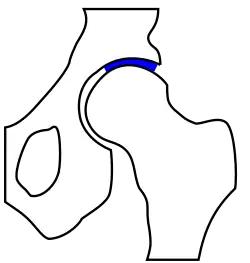

Klassische Ursache einer Arthrose stellt die Dysplasie von Gelenken dar. Am Beispiel der Hüfte wird deutlich, dass die mechanisch am meisten belastete Zone bei einer physiologischen Hüftstellung eine deutlich größere Fläche darstellt als bei einer dysplastischen Hüfte. Die Belastungen durch die auf das Gelenk einwirkenden Kräfte sind von der Gelenkform jedoch weitgehend unabhängig. Sie verteilen sich im Wesentlichen auf die Hauptbelastungszone(n). Dadurch wird bei einer kleineren Zone eine höhere Druckbelastung als bei einer größeren auftreten. Die biomechanische Druckbelastung des Gelenkknorpels ist somit bei einer dysplastischen Hüfte größer als bei physiologischer Hüftstellung. Diese Gesetzmäßigkeit wird allgemein ursächlich für das gehäufte Auftreten arthrotischer Veränderungen an von der anatomischen Idealform abweichenden tragenden Gelenken gesehen.